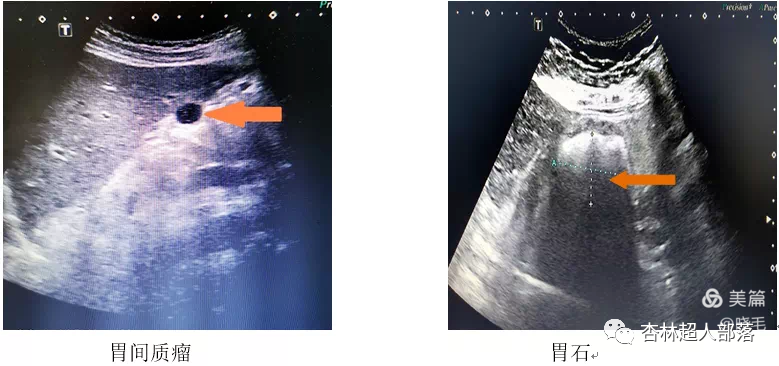

下面我们看看胃肠超声扫描出来的

这些典型病例图像吧。